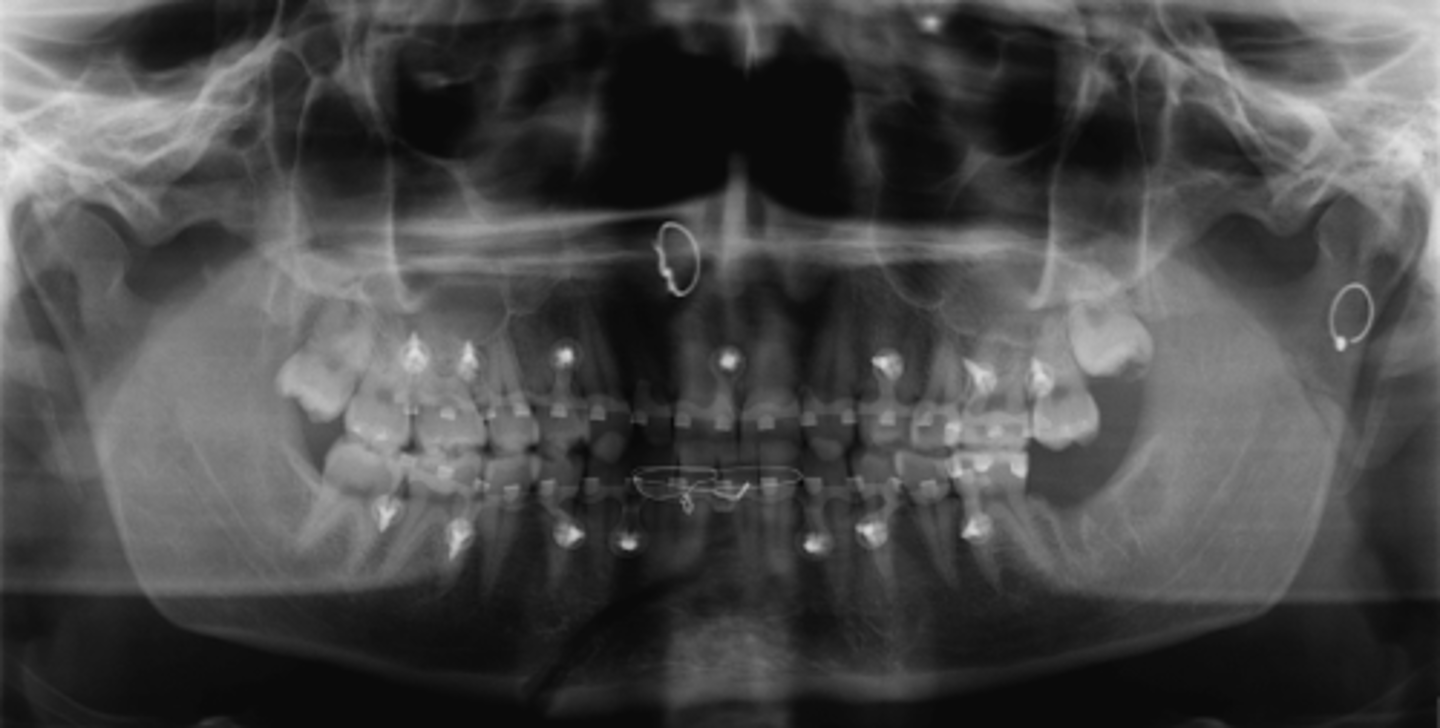

Subcondylar

PANOREX showing this fracture pattern. Where is this fracture located?

- Angle

- Subcondylar

- Body

- Coronoid

- Ramus